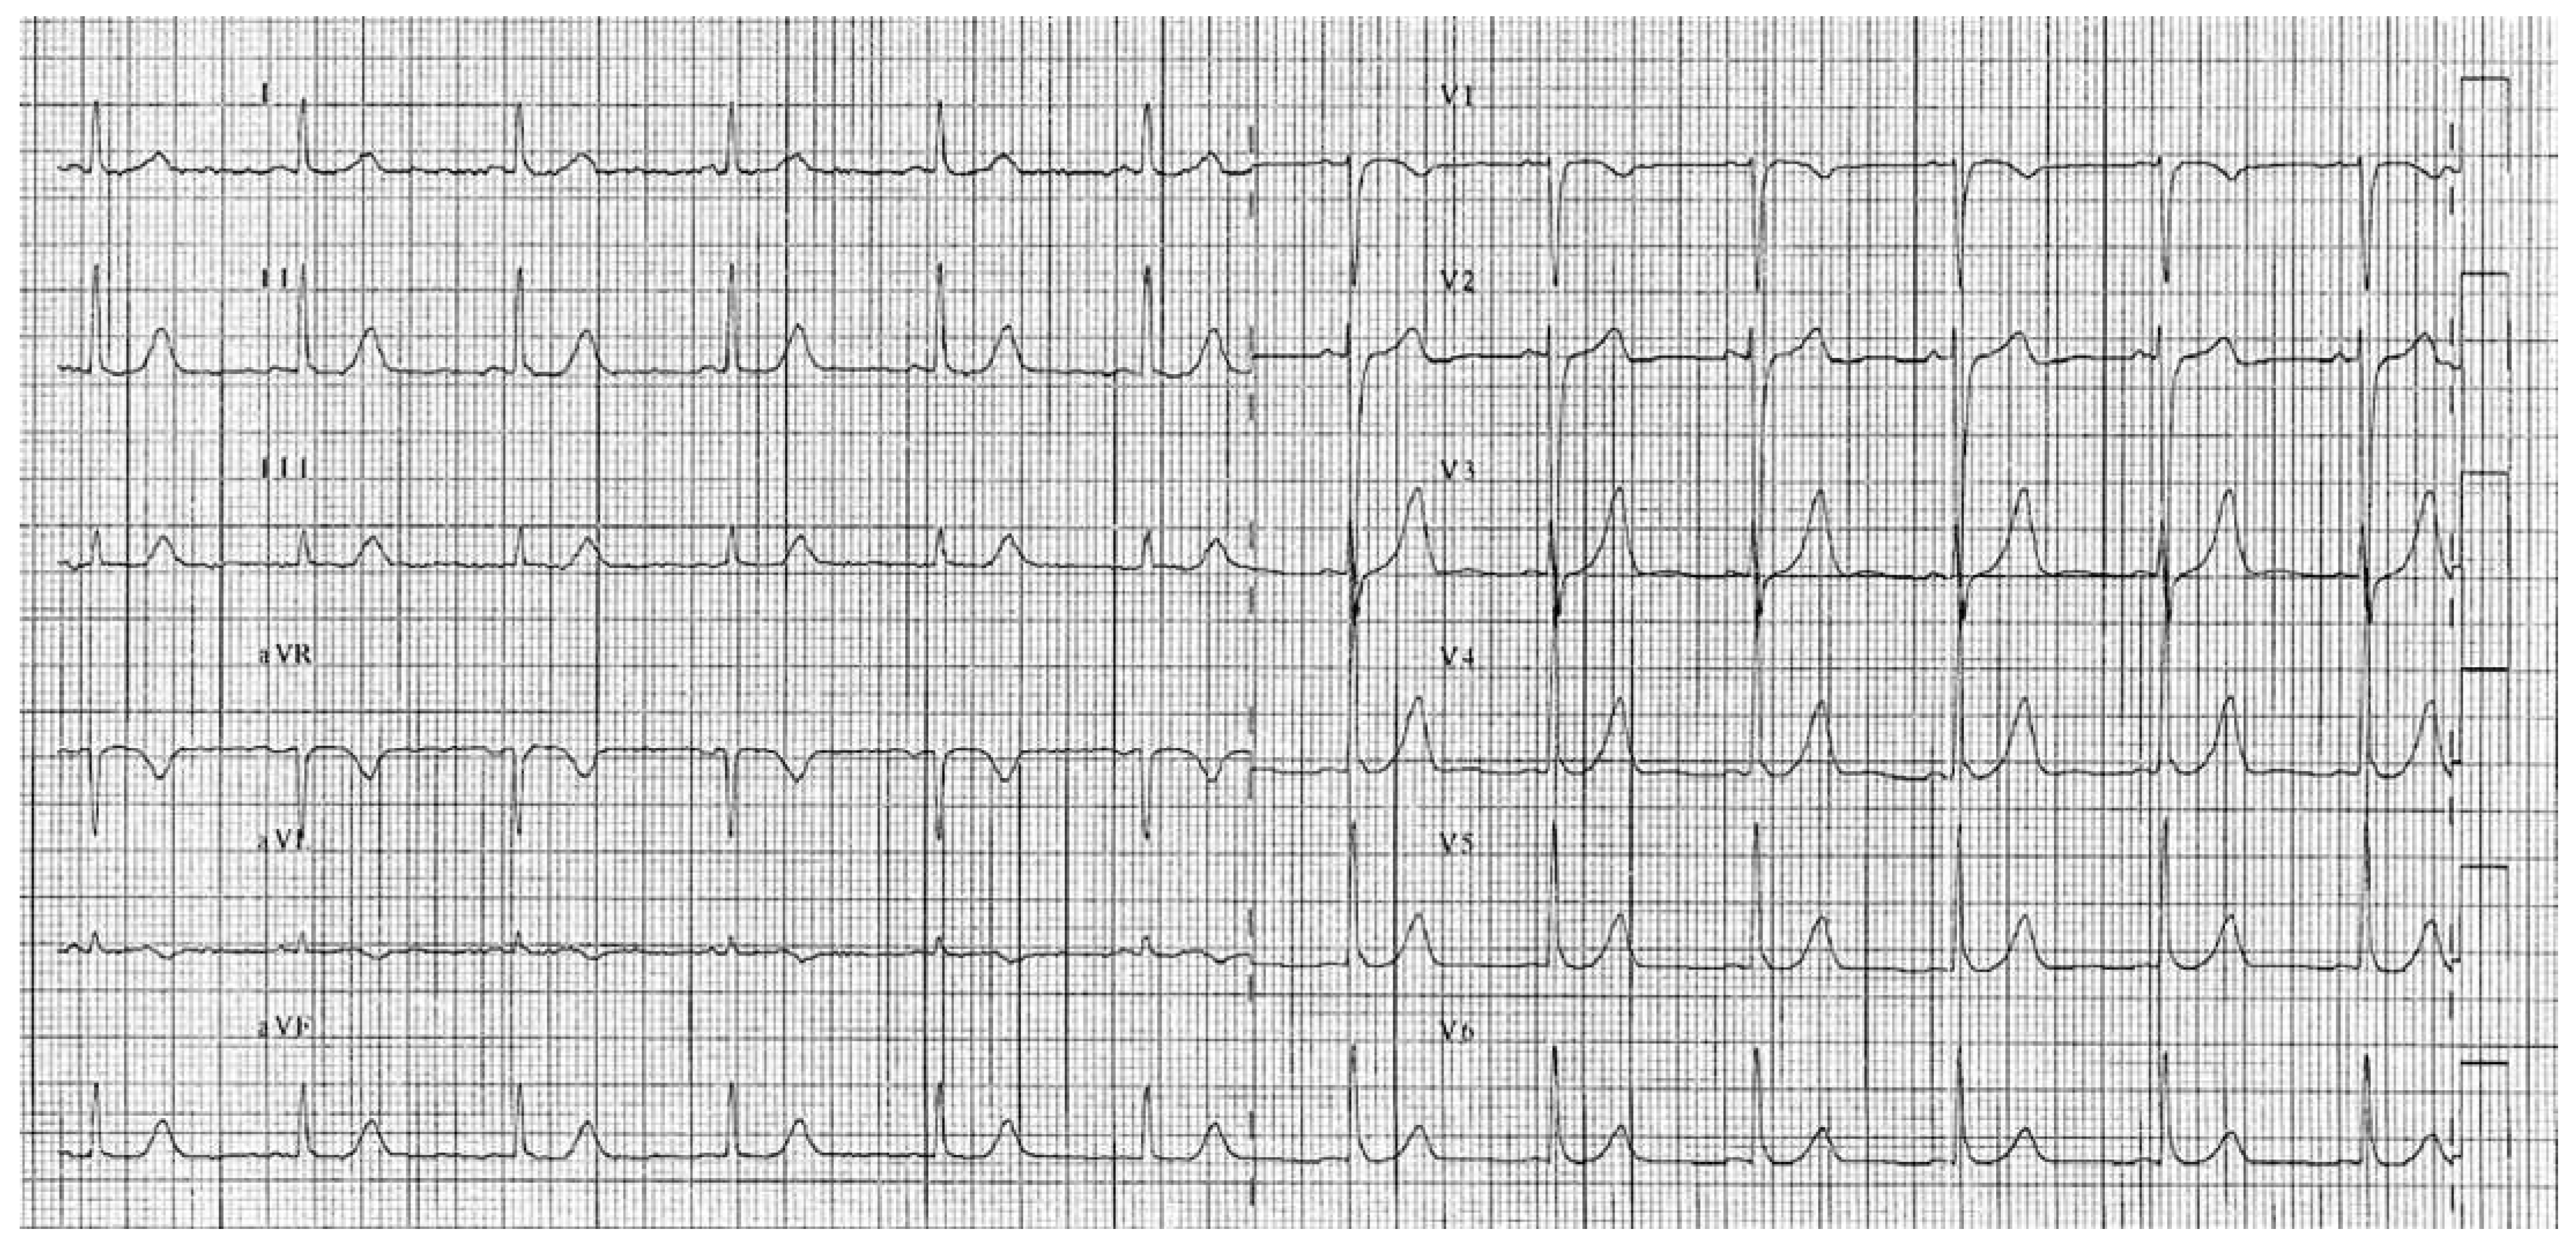

The current report describes a 30-year-old Caucasian woman who came to our attention because she presented with a rapidly progressing bilateral proprioceptive ataxia, spinothalamic hypoaesthesia and gait impairment. Two years before, the patient had experienced an analogous neurological episode. Medical history, clinical, laboratory and imaging findings supported the diagnosis of an acute multiple sclerosis relapse according to McDonald criteria. Intravenous, and later oral, steroid therapy was implemented with suboptimal patient relief. Ten days later the patient was transferred to the coronary care unit because of acute typical chest pain. With the exception of ongoing significant neurological impairment no further clinical findings nor haemodynamic compromise were present. The electrocardiogram (ECG) showed diffuse ST-segment depression (Figure 1A), the corrected QT-interval was not prolonged (409 msec) and brain natriuretic peptide (BNP) levels were not measured. Transthoracic echocardiography showed akinetic basal segments (Figure 1B: 4-chamber view, end-systole: arrows) and apical hypercontractility with slightly reduced (45–50%) left ventricle ejection fraction (LVEF%) (see online Video 1: four-chamber view). These findings were inconsistent with a moderate increase in serum troponin (peak 3.5; reference value <0.09). The patient immediately underwent selective coronary angiography, which disclosed the absence of any coronary stenosis or dissection (Figure 1C–D). Although cardiac magnetic resonance imaging (MRI) was not performed, the diagnosis of myocarditis was reasonably rejected owing to the absence of systemic inflammation (normal C-reactive protein, leucocyte and procalcitonin values), negative bacterial blood cultures and viral tests. Phaeochromocytoma was excluded because of normal 24-hour urine fractionated catecholamines and metanephrines. Two days later the ECG showed complete spontaneous normalisation (Figure 2). Thus, the diagnosis of basal (inverted) Tako-Tsubo cardiomyopathy (TTC) was retained.

Figure 2. Post-acute phase ECG demonstrates complete normalisation of repolarisation within two days.